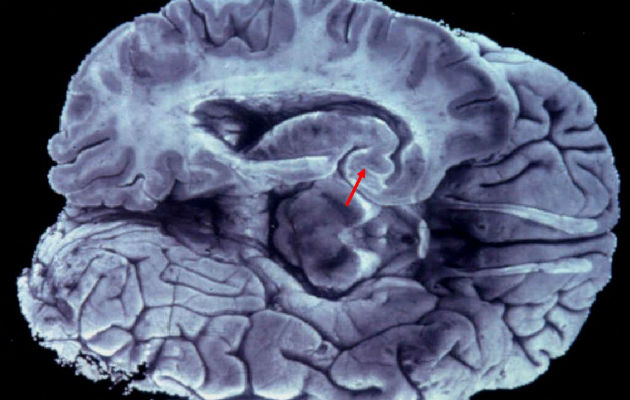

Un grupo de físicos y biólogos ha desarrollado una nueva técnica de microscopía que, por primera vez, permite obtener imágenes de todas las células dentro de un área determinada del tejido cerebral vivo, lo que permitirá mejorar el conocimiento del cerebro. La revista científica Cell acaba de publicar este hallazgo, fruto de una investigación transfronteriza en la que colaboran la Universidad del País Vasco y el centro vasco de neurociencias Achucarro, en España, y la Universidad de Burdeos (Francia). Según informó este viernes la universidad vasca, los métodos de microscopía existentes hasta ahora para investigar el tejido cerebral vivo se limitaban a visualizar solo las células previamente marcadas por los científicos, con lo que, por limitaciones técnicas, no todas las células de una región cerebral determinada podían ser etiquetadas por los investigadores. Ello restringía la visión de la zona cerebral a estudiar y la comprensión de cómo se organizan y actúan las células cerebrales, que están altamente interconectadas. Ahora, con la nueva técnica de microscopía, denominada "Sushi" (acrónimo del nombre en inglés, "Super-resolution Shadow Imaging"), los científicos pueden "etiquetar" de una pasada el minúsculo espacio, lleno de líquido, que rodea las células cerebrales, y evitan así tener que marcar individualmente todas las células del área que se quiere analizar. Uno de los firmantes del trabajo, el doctor sueco Jan Tonnesen, investigador del departamento de Neurociencias de la Universidad pública vasca y que trabaja en el centro Achucarro, destacó que la nueva técnica es "revolucionaria" porque permite visualizar "simultáneamente" todas las células en una región determinada del tejido cerebral vivo. "Antes encontrábamos espacios en blanco en las imágenes de microscopía, ya que no podíamos etiquetar todas las células al mismo tiempo, hecho que nos resultaba muy limitante", añadió. Tonnesen destacó que, a partir de ahora, la nueva técnica permitirá a los neurocientíficos ver todas las células del área de estudio que sitúen bajo la lente del microscopio, así como sus interacciones, lo que posibilizará avanzar en el conocimiento de las funciones cerebrales, "tanto en el órgano sano como cuando enferma". El hallazgo es producto de un proyecto interdisciplinar desarrollado entre el doctor Tonnesen y un grupo de investigación dirigido por el profesor Valentin Nagerl, de la Universidad de Burdeos.